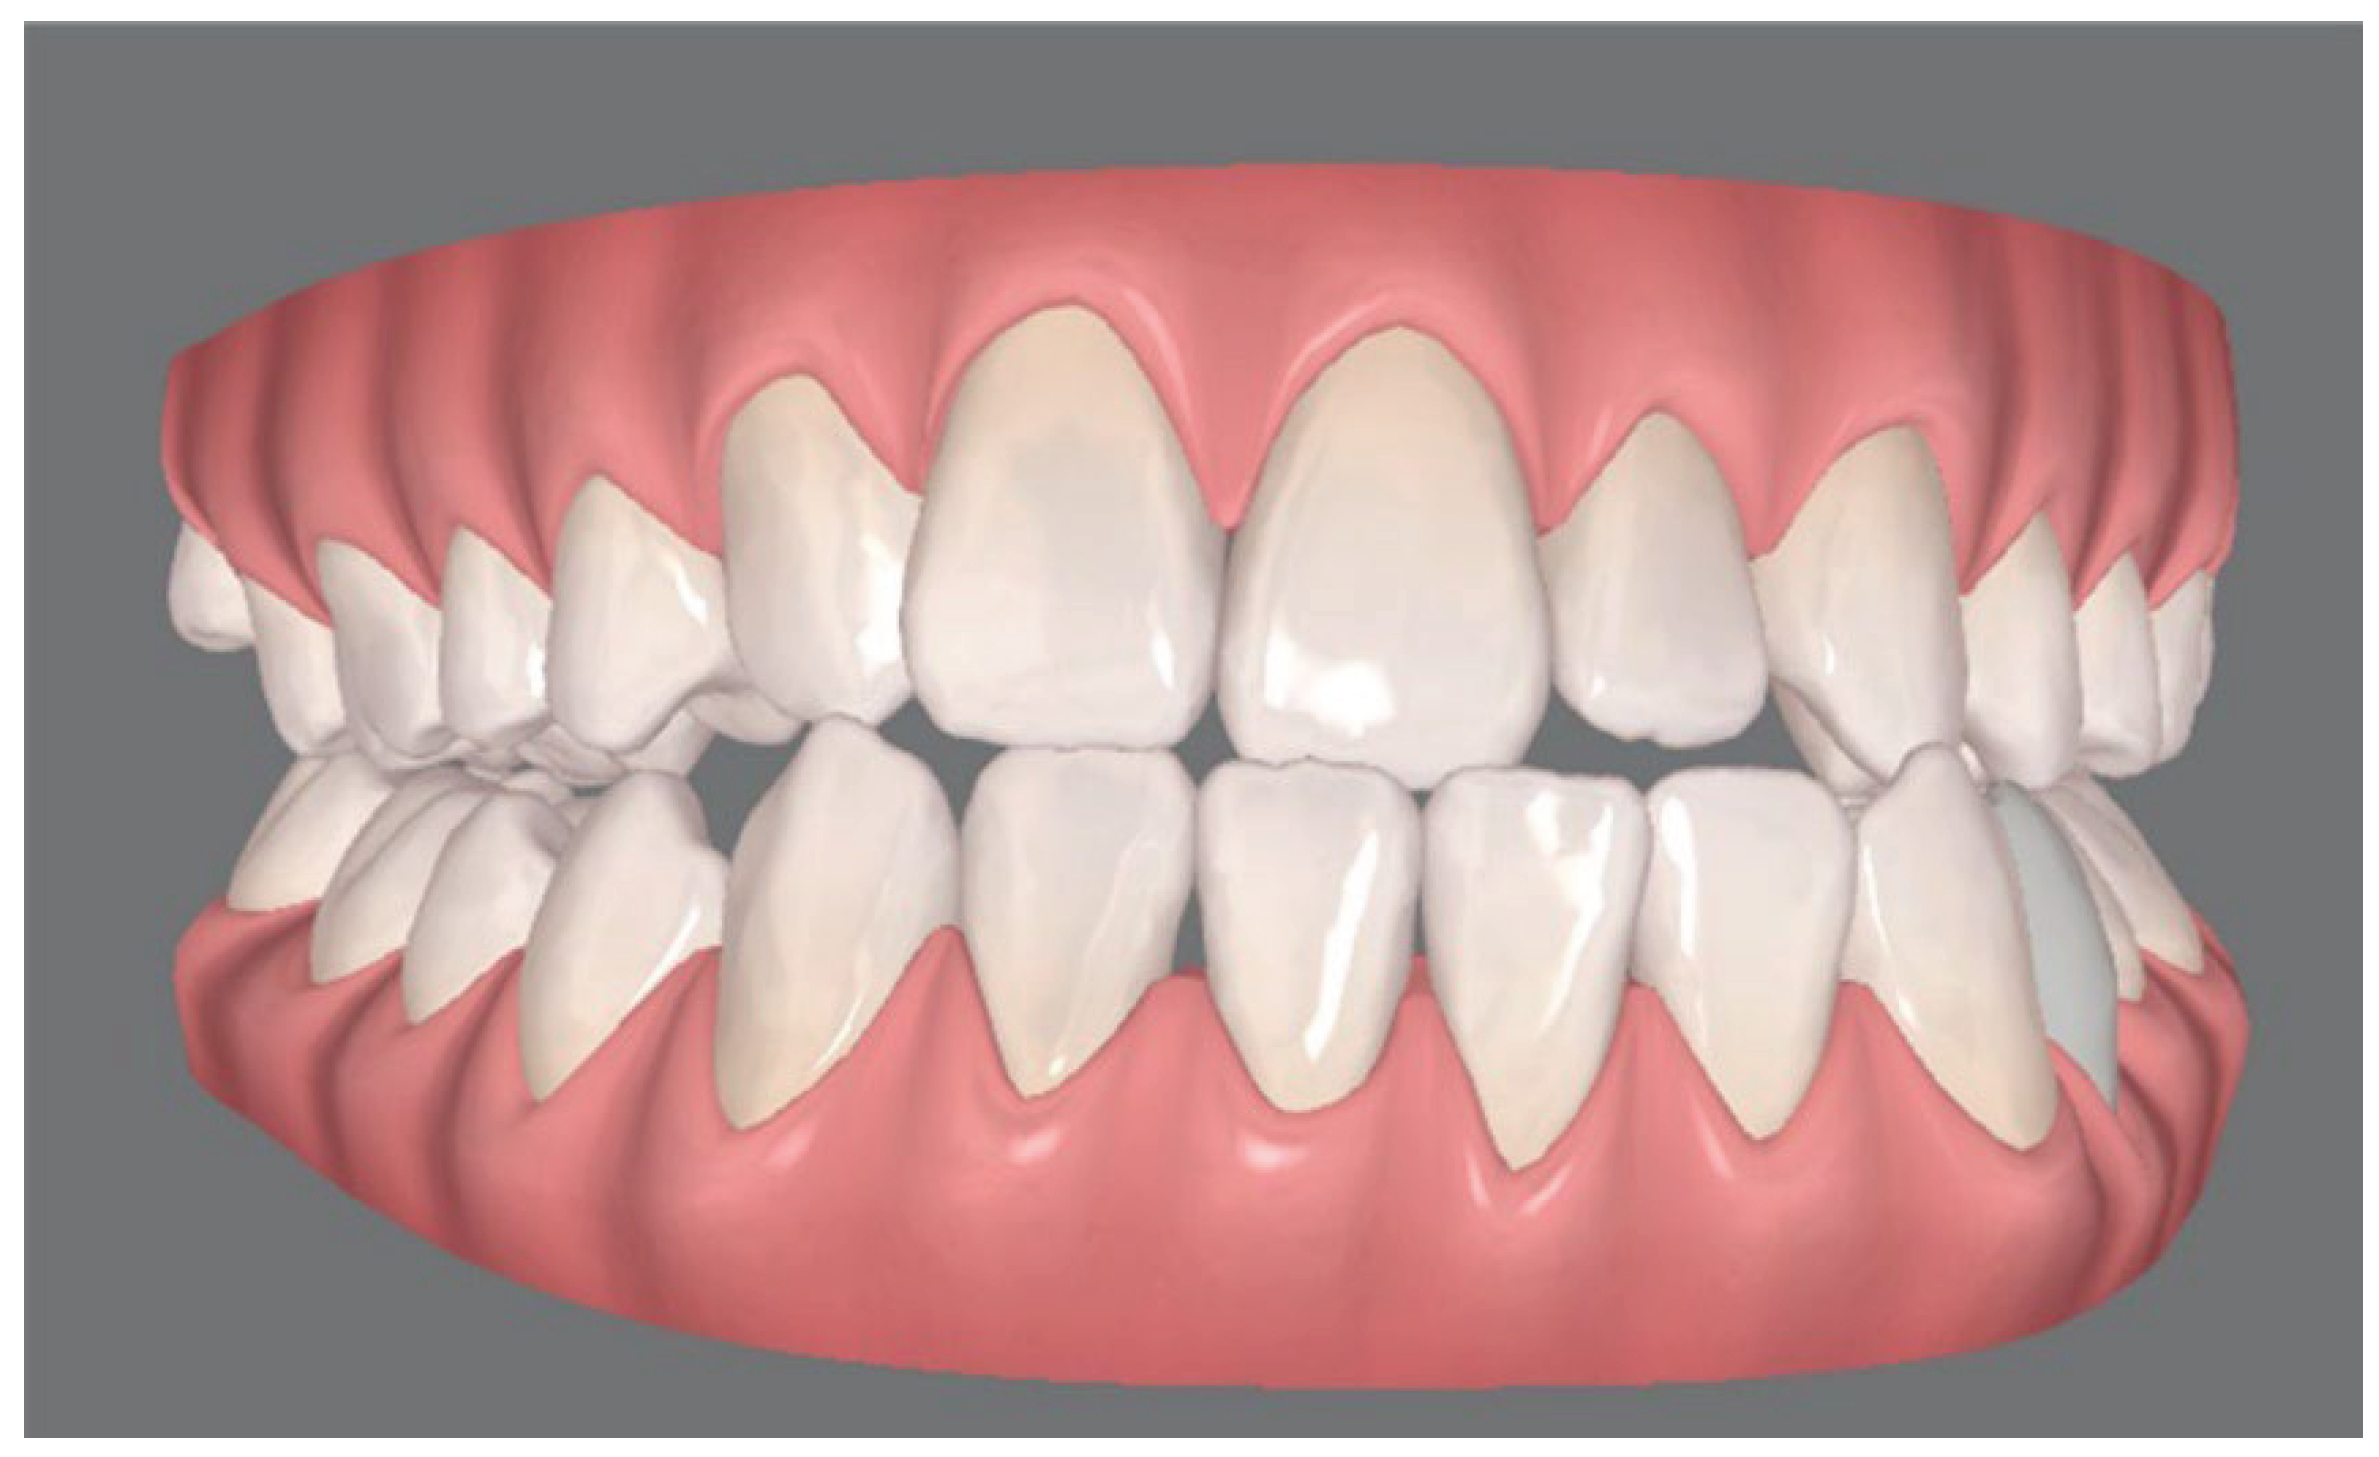

Figure 3. a, final occlusion obtained by clear aligner pre-surgical preparation. Note that the patient underwent an extraction of the left lower first premolar in order to avoid the mandibular osteotomy and allow the orthodontic decompensation; b, virtual simulation of the final occlusion elaborated with clin check software.

Pre surgical orthodontic treatment time was similar for the two techniques. The fixed appliance patients were treated for an average of 16.3 ± 4 months (range 9 – 22 months) (p > 0.05 n.s.), with an average of 10.2 ± 1.6 appointments (p<0.05). The Invisalign patients required an average of 18.4 ± 3 months (range 11 - 23) pre-surgically, with an average of 5.1 ± 0.8 appointments. The figures refer to a UCLP patient of the sample group treated with a two-piece Le Fort I osteotomy with a mandibular osteotomy. (Figure 5).